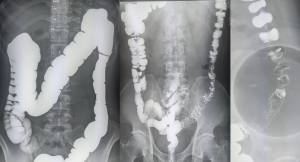

关于钡灌肠检查,您了解吗 [2024-01-08]

钡灌肠 是指经肛门插管灌注适量钡剂及适量气体在X线透视下诊断结肠及直肠疾病的检查方法。可以观察肠道有无扩张、狭窄,有无肠壁黏膜的破坏及隆起...